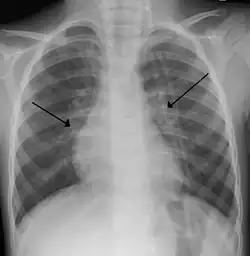

X-ray of a child with RSV bronchiolitis showing the typical bilateral perihilar fullness

Chest X-ray findings in children with RSV bronchiolitis are generally nonspecific and include perihilar markings, patchy hyperinflation, and atelectasis.[20] However, the American Academy of Pediatrics (AAP) does not recommend routine imaging for children with presumed RSV bronchiolitis because it does not change clinical outcomes and is associated with increased antibiotic use.[20][5] Chest X-ray is sometimes considered when the diagnosis of bronchiolitis is unclear or when there is an unexpected worsening.[5] In adults with RSV infection, chest films are often normal or demonstrate nonspecific changes consistent with viral pneumonia, such as patchy bilateral infiltrates.[45]